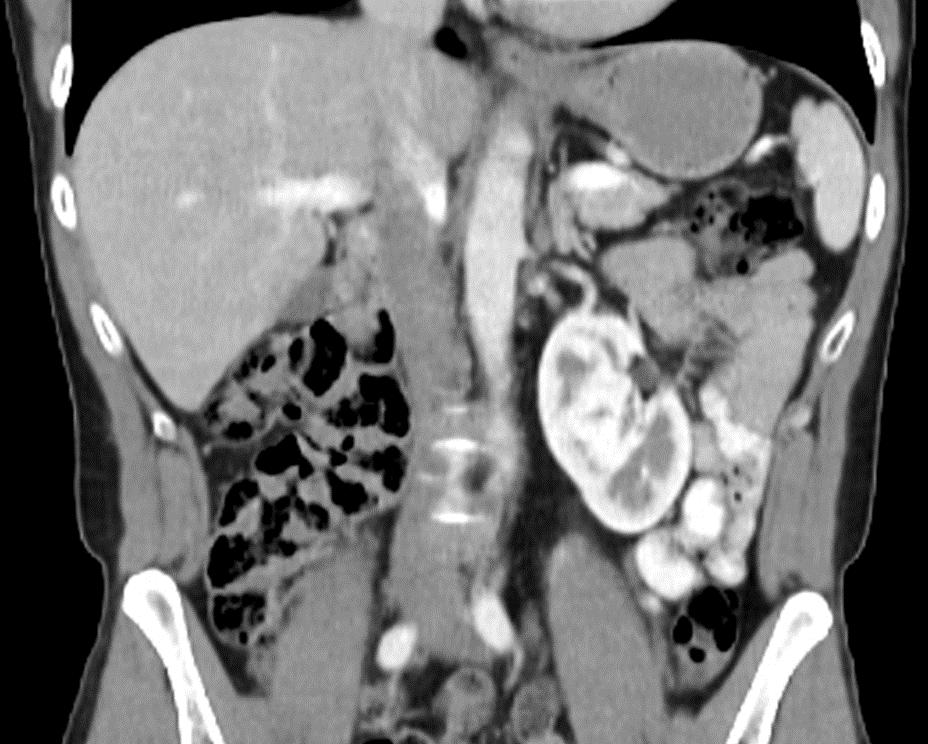

Souhrn: Úvod: Indikace nefroureterektomie (NUE) pro uroteliální tumory horních cest močových (UTUC – upper tract urothelial carcinoma) jsou poměrně jasné, otázkou zůstává technika provedení NUE a též indikace lymfadenektomie (LAE) během NUE. Metod provedení NUE je široké spektrum (otevřený výkon, laparoskopie, endoskopie), v zásadě máme fázi nefrektomie a fázi ureterektomie a event. ještě LAE, přičemž se jednotlivé metodiky kombinují. Otevřená NUE zůstává dominantou pro pokročilé nádory, jinak se již široce využívají miniinvazivní techniky. Po dlouhých letech provádění postupně tří metod laparoskopické NUE jsme se zakoupením robotického systému da Vinci Xi mohli přejít na metodiku kompletní miniinvazivní roboticky asistované NUE (RA-NUE), bez změny polohy, bez nutnosti endoskopie. Naši techniku prezentujeme na videu. Soubor: Od července 2021 do prosince 2025 jsme u 109 případů UTUC provedli NUE u 93 (85,3 %) a ledvinu šetřící výkon u 16 (14,7 %). RA-NUE z NUE u 43 (46,2 %) vybraných nemocných, u 5 z nich s LAE (high-risk cT2–3 či high-grade a cN0). Dvakrát byla provedena ještě RA-NUE pro finálně jinou histologii než uroteliální karcinom – světlobuněčný renální karcinom a xantogranulomatózní pyelonefritidu. U dalších 5 (4,6 %) byla provedena RA-NUE s následnou RA radikální cystektomií. Laparoskopická NUE u 11 (10,1 %), při nedostupnosti robotického systému. K otevřenému výkonu (34; 31,2 %) byli indikováni nemocní s pokročilými nálezy, výrazně obézní, s předchozí rozsáhlejší nitrobřišní operací. Technika operace prezentovaná na videu: RA-NUE vlevo s horní LAE: je užit čtyřramenný systém da Vinci Xi, močový katetr, poloha na boku 60°. Nejkaudálnější port je 12mm pro možnost aplikace stapleru, ostatní jsou 8mm. Asistentský port je mediálněji, 15mm pro finální zavedení extrakčního sáčku Endocatch™ bag II. Kamera 30°, ProGrasp™, bipolární grasper Maryland™, monopolární nůžky či pečeticí nástroj SynchroSeal™. Výkon se začíná standardní nefrektomií, jen se časně klipuje ureter k minimalizaci diseminace z horních cest močových do měchýře. Následuje paraaortální, resp. parakavální LAE pomocí nůžek či pečeticího nástroje. Bez redokování systému je pokračováno excizí močovodu kraniokaudálně in toto až do pánve. Testikulární žíla je většinou šetřena, u žen bývá šetřena ovarická žíla a celá adnexa se odklápí mediálně. Na videu je žena po panhysterektomii. Ureter je excidován z močového měchýře s terčíkem a defekt měchýře zašit s V-Loc® 90 3-0. Steh se na měchýř nasazuje ještě před kompletním odstřižením ureteru užitým pro trakci. Horní LAE je možno doplnit i na závěr výkonu. Extrakce močového katetru 6. pooperační den po elektivní cystoradiografii (CRG). Intravezikální jednorázové podání cytostatika neužíváme. Výsledky: Celkem 45 RA-NUE u 29 mužů a 16 žen, průměrný věk 71,4 ± 9,3 (47,7–86,1) roku, body mass index 28,0 ± 3,77 (20,2–35,7) kg/m 2, u 38 popsanou descendentní technikou, 7× s redockingem na pánevní část v Trendelenburgově poloze. Z těchto sedmi bylo celkem 2× pro tumor distálního ureteru zahájeno pánevní fází, 1× excidován i divertikl měchýře a 4× vynucená změna ve druhé fázi na Trendelenburg (2× větší tumor distálního ureteru, 1× přetržen ureter juxtavezikálně a intramurální část excidována TURem a 1× z preparátu RA nefrektomie vysloveno podezření na UTUC a doplněna ureterektomie). Průměrný čas operace u všech 153 ± 29 (99–240) min; u descendentní RA-NUE 143 ± 21 (99–199) min, s LAE 189 ± 35(164–240) min. U posledních 17 výkonů byl užit SynchroSeal™. Krevní ztráta byla 55,8 (0–400) ml. U 5 pacientů (4 ženy, 1 muž) byla provedena LAE – 4× LAE

horní u tumorů pánvičky, 1× LAE pánevní u tumoru distálního ureteru – zde byla provedena zmíněná změna polohy na záda a excize distálního ureteru a LAE. Průměrný počet uzlin byl 6 (2–10). Hilové renální cévy byly přerušeny robotickým staplerem 25× en bloc a 2× separovaně, 1× separovaně externím staplerem a 17× separovaně pomocí uzamykatelných klipů asistentem. Drén byl použit 15×. Hmotnost preparátu byla 496 (128–1 045) g. Histologicky byl popsán 43× UC pTa–pT3 (1× pN1), 1× světlobuněčný renální karcinom pT2aG3, 1× xantogranulomatozní pyelonefritida. Doba hospitalizace byla 7,2 (3–18) dní. Cévka byla odstraněna v průměru za 12,8 ± 11,4 (5–58) dne (9× byla ponechána déle než 14 dní pro únik kontrastní látky při CRG). Komplikace (krom úniku ze sutury měchýře) dle Clavien-Dindo 1× typ 2 (prolongovaný chylózní ascites řešený konzervativně, trvání 2 měsíce). Dlouhodobé sledování zatím není dostupné, 1× lokální recidiva tumoru G3 řešena cystektomií. Závěr: RA-NUE se stala na našem pracovišti standardní metodou NUE a nahradila laparoskopický přístup. Zatím optimálně u nálezu, kde není indikována LAE. Hlavní relativní komplikací je prolongovaný urinózní únik ze sutury měchýře. Otevřená NUE stále zůstává v armamentáriu pro vybrané případy nevhodné k RA-NUE (pokročilé tumory, výrazná obezita, anamnéza extenzivní intraabdominální chirurgie).

Klíčová slova: nefroureterektomie – laparoskopie – robot

Summary: Introduction: The indications for nephroureterectomy (NUE) for upper tract urothelial carcinoma (UTUC) are relatively clear, but questions remain regarding the technique used to perform NUE and the indications for lymphadenectomy (LND – lymph node dissection) during NUE. There is a wide range of NUE techniques (open surgery, laparoscopy, endoscopy). Basically, there is a nephrectomy phase and an ureterectomy phase, and possibly also LND, with individual techniques being combined. Open NUE remains the dominant technique for advanced tumors, otherwise minimally invasive techniques are widely used. After many years of gradually performing three methods of laparoscopic NUE, we were able to switch to the complete minimally invasive RA-NUE technique with the purchase of the da Vinci Xi robotic system. No change of position, no need for endoscopy. We present our technique in a video. Method: From July 2021 to December 2025, we performed NUE in 93 (85.3%) of 109 UTUC cases and kidney-sparing surgery in 16 (14.7%). RA-NUE from NUE in 43 (46.2%) selected patients, 5 of whom had LND (high-risk cT2–3 or high-grade and cN0). RA-NUE was performed twice for a final histology other than UC – clear cell renal carcinoma and xanthogranulomatous pyelonephritis. In another 5 (4.6%) patients, RA-NUE was performed followed by RA radical cystectomy. Laparoscopic NUE was performed in 11 (10.1%) cases when the robotic system was unavailable. Open surgery (34; 31.2%) was indicated for patients with advanced findings, who were significantly obese, or who had undergone previous extensive intraabdominal surgery. The surgical technique presented in the video: RA-NUE on the left with upper lymphadenectomy: A 4-arm da Vinci Xi system, urinary catheter, and 60° lateral position are used. The most caudal port is 12 mm for stapler application, the others are 8 mm. The assistant port is more medial, 15 mm for final insertion of the Endocatch™ bag II extraction bag. Camera 30°, ProGrasp™, Maryland™ bipolar grasper, monopolar scissors, or SynchroSeal™ sealing tool. The procedure begins with a standard nephrectomy, but the ureter is clipped early to minimize UC dissemination into the bladder. This is followed by paraaortic or paracaval LND using scissors or a sealing device. Without re-docking the system, the ureter is excised craniocaudally in this direction up to the pelvis. The testicular vein is usually preserved,

Ces Urol 2026; 30(1): 16–18

and in women, the ovarian vein is preserved and the entire adnexa is folded medially. The video shows a woman after a panhysterectomy. The ureter is excised from the bladder with the bladder cuff and the bladder defect is sutured with V-Loc® 90 3-0. The suture is applied to the bladder before complete transection of the ureter, which is used for traction. The upper LND can also be performed at the end of the procedure. Extraction of the urinary catheter on the 6th postoperative day after elective cystoradiography (CRG). We do not use intravesical single-dose cytostatics. Results: A total of 45 RA-NUE in 29 men and 16 women. Average age 71.4 ± 9.3 (47.7–86.1) years. Body mass index 28.0 ± 3.77 (20.2–35.7) kg/sqm. In 38 cases, the described descending technique was used, 7 times with redocking to the pelvic part in the Trendelenburg position. Of these 7 cases, 2 were for distal ureteral tumors started in the pelvic phase, 1 was excised with a bladder diverticulum, and 4 were forced to change to the Trendelenburg position in the second phase (twice for larger distal ureteral tumors, once for a ruptured ureter juxtavesically and intramural part excised by TUR, and once for suspected UTUC based on RA nephrectomy preparation and supplemented by ureterectomy). The average duration of surgery for all 153 ± 29 (99–240) min – for descending RA-NUE 143 ± 21 (99–199) min, with LND 189±35 (164–240) min. SynchroSeal™ was used in the last 17 procedures. Blood loss was 55.8 (0–400) mL. LND was performed in 5 patients (4 women, 1 man) – 4 upper LNDs for pelvic tumors, 1 pelvic LND for a distal ureter tumor – here, the aforementioned change to the supine position was performed, along with excision of the distal ureter and LND. Average number of nodes was 6 (2–10). Hilum renal vessels interrupted by robotic stapler 25× en bloc and 2× separately, 1× separately by external stapler and 17× separately by lockable clips by assistant. Drain used 15×. The weight of the specimen was 496 (128–1,045) g. Histologically, as mentioned, 43× urothelial carcinoma (UC) pTa–pT3 (1× pN1), 1× clear cell renal carcinoma pT2aG3, and 1× xanthogranulomatous pyelonephritis were confirmed. The length of hospitalisation was 7.2 (3–18) days. The catheter was removed on average after 12.8±11.4 (5–58) days (9× left in place for longer than 14 days due to contrast agent leakage during CRG). Complications (except for leakage from the bladder suture) according to Clavien-Dindo – 1× type 2 (prolonged chylous ascites treated conservatively, duration 2 months). Long-term follow-up is not yet available, 1× local recurrence of G3 tumor treated with cystectomy. Conclusion: RA-NUE has become the standard NUE method at our facility, replacing the laparoscopic approach. So far, it has been optimal for findings where LND is not indicated. The main relative complication is prolonged urinary leakage from the bladder suture. Open NUE remains in the armamentarium for selected cases unsuitable for RA-NUE (advanced tumors, severe obesity, history of extensive intra-abdominal surgery).